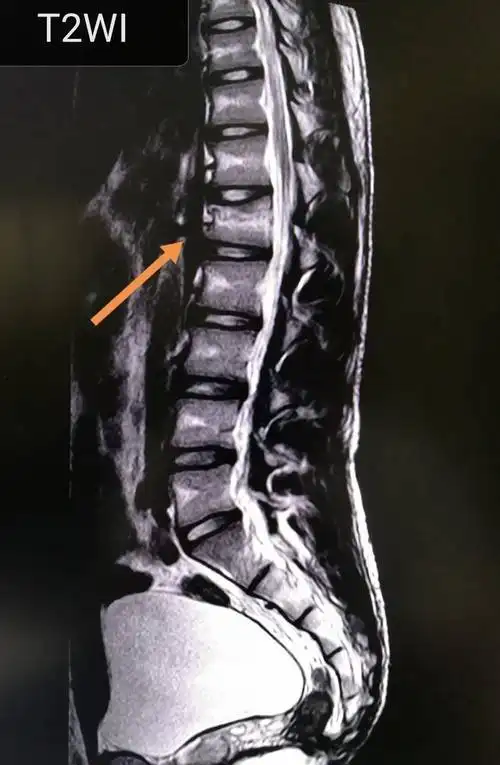

腰椎压缩性骨折新鲜原创

腰椎压缩性骨折新鲜